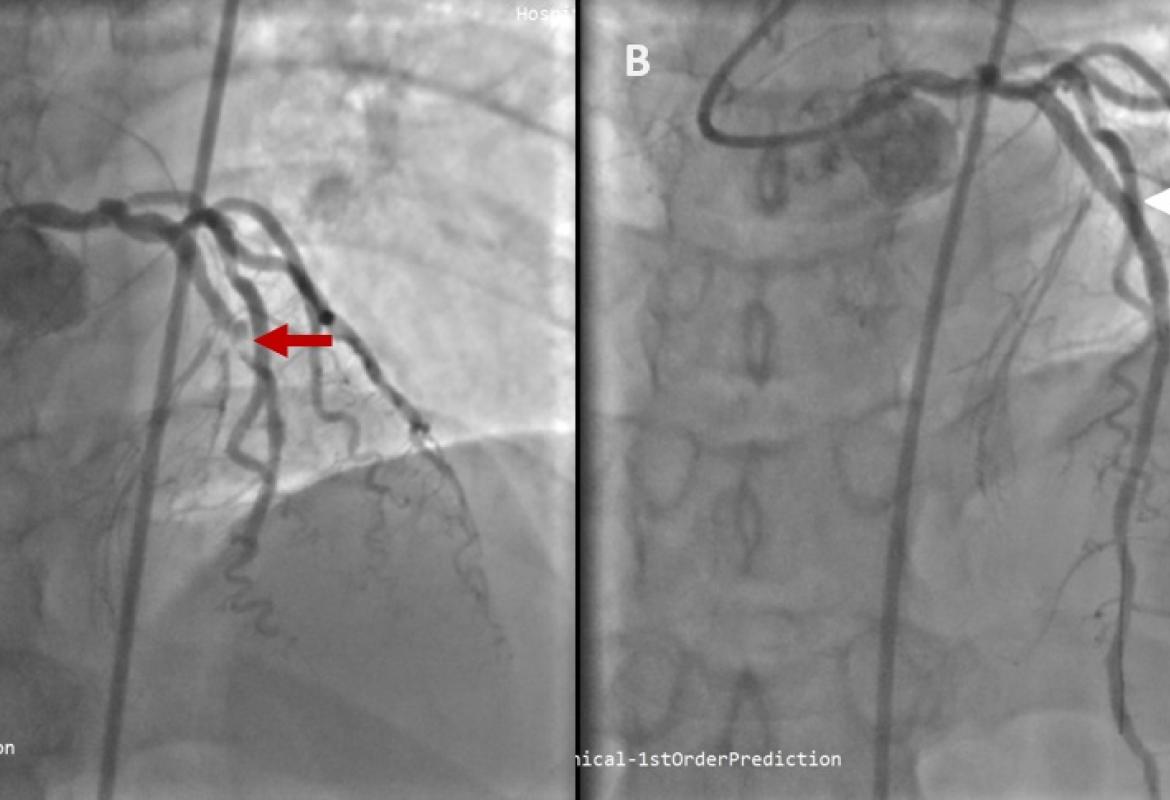

Early Recognition and Intervention of De Winter Syndrome: A Case Report

Case Report 27 Jan, 2025

Wan Asyraf Wan Zaidi

• Read more about Wan Asyraf Wan Zaidi

Wan Nafisah Wan Yahya

• Read more about Wan Nafisah Wan Yahya

Nasheeda Saeed

• Read more about Nasheeda Saeed

Wei Ching Mow

• Read more about Wei Ching Mow

Rathika Rajah

• Read more about Rathika Rajah